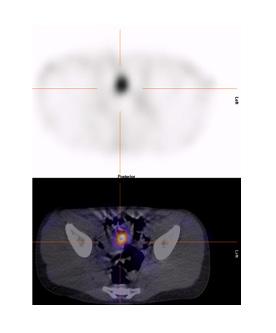

Figure 4 : Patient de 13 ans. Rectorragies avec chute de l’hémoglobine. Administration de Zantac IV deux heures avant la scintigraphie. Mise en évidence d’élution au niveau du duodénum et du grêle mais également d’un diverticule de Meckel au flanc droit, près du rein, mieux identifié sur l’étude tomographique. Étude dynamique ( A ) et statique (B) en incidence antérieure, rendu 3D du SPECT (C) et image de fusion (D).

Dans notre expérience, l’étude SPECT-TDM faible permet de confirmer les trouvailles planaires et de mieux le localiser par rapport aux structures normales pour la planification opératoire (figure 7 ). Dans notre expérience également, quoiqu’aucun diverticule de Meckel n’ait été identifié uniquement sur l’étude

Meckel n’ait été détecté uniquement sur SPECT, le SPECT/TDM a offert une meilleure localisation, une clarification des résultats douteux sur l’imagerie planaire et pour certains un diagnostic alternatif.